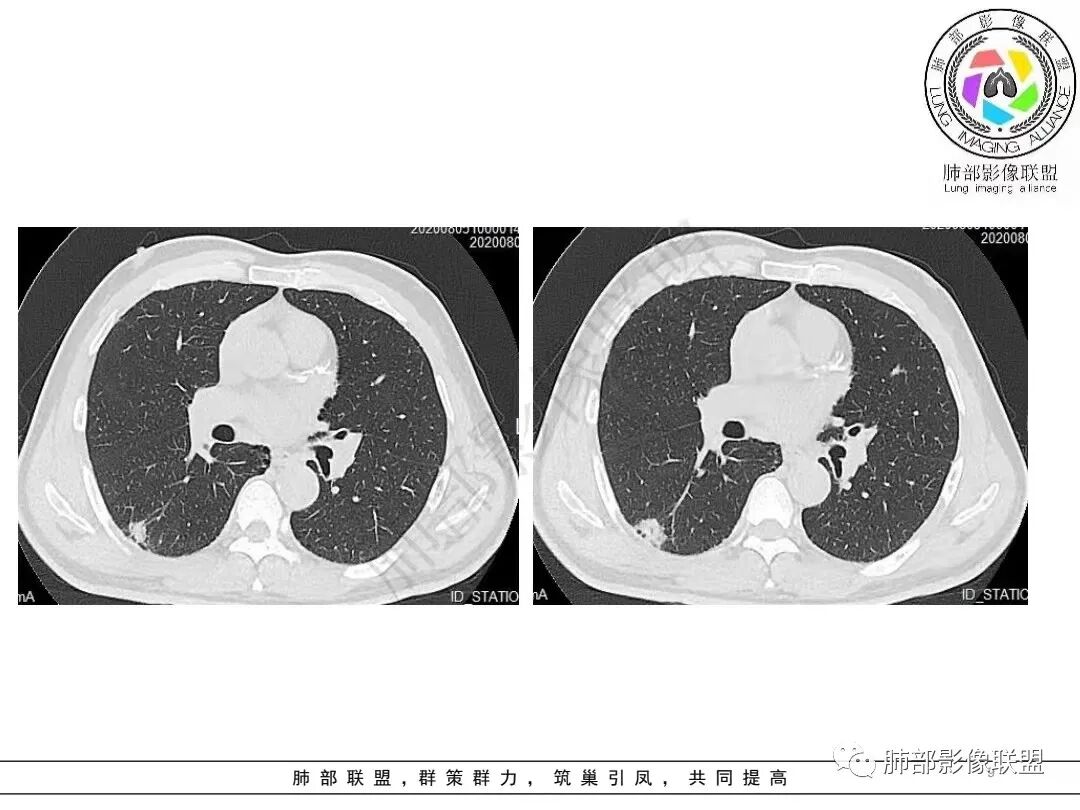

2.病例二:30岁女性,发现病灶6个月前有咳嗽咳痰及治疗史,肿瘤标志物阴性。左肺下叶胸膜下结节影,整体较膨隆,局部边缘较平直,可见毛刺,同样可见磨玻璃密度区,病灶内可见空泡征,周围可见细小毛刺及多发棘突影,同样外围病灶支气管情况难以判断。邻近肺组织内可见多发微小结节影。病灶张力不高,未见分叶及胸膜牵拉,由于纵隔窗图像太少,不宜判断胸膜下脂肪间隙有无受累,可疑胸膜下有微量积液。

综合分析:两份病例都是位于胸膜下的孤立结节,同样具有锯齿状边缘,有细毛刺、空泡。病例一老年男性+CEA显著升高,常规恶性病变肯定是要考虑;至于病例二青年女性,肿瘤标志物阴性,在未见非常典型恶性征象情况下,临床通常会优先选择炎性病灶进行处置,病灶持续存在,复查无变化或出现进展,则应想到新生物可能,而选择穿刺或其他进一步检查。